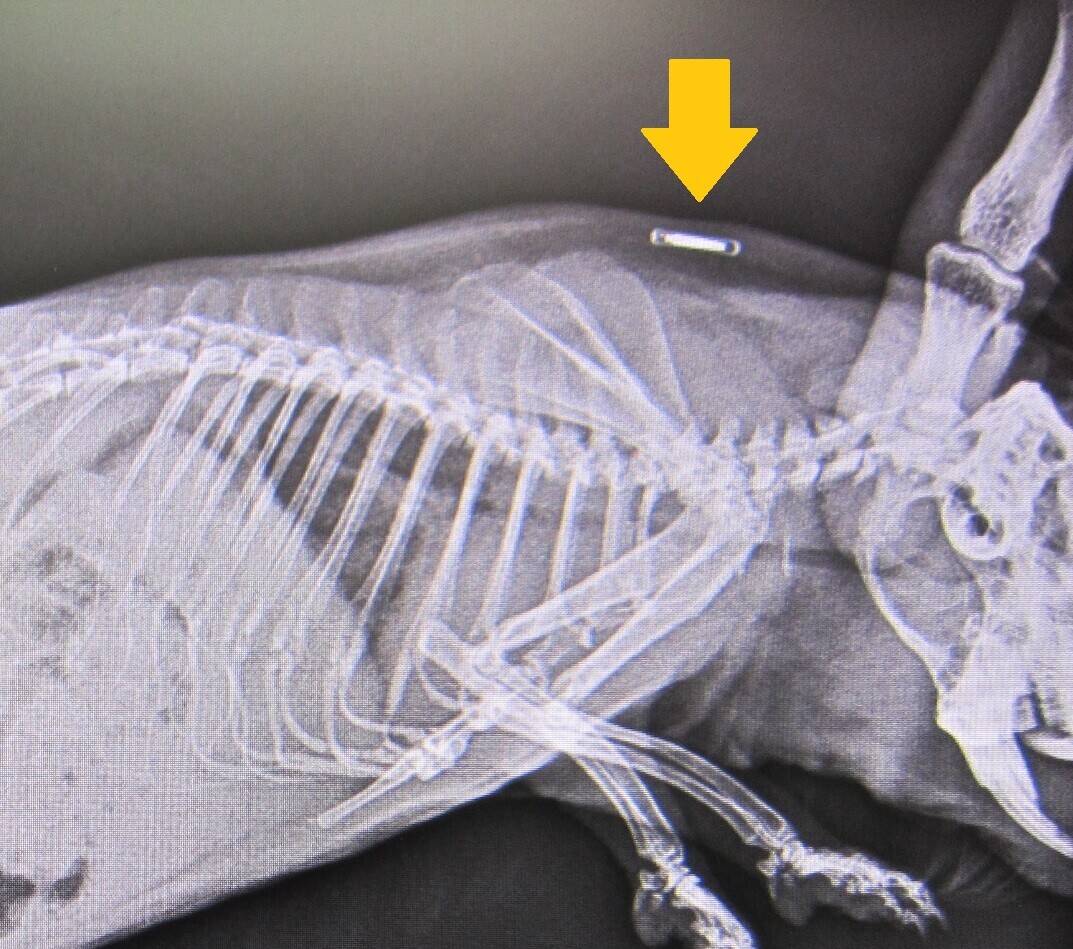

続いては、コチラ。

なかよし広場でおなじみのモルモットです。

注目してほしいのはココ!

これ、なんだかわかりますか?

実はこれ、マイクロチップなんです。

なかよし広場にいるたくさんのモルモットをはじめ、園内動物の多くには、

個体管理をするために1頭1頭マイクロチップを埋め込んでいるのです。

専用のリーダーで読み取れば、瞬時にマイクロチップの番号が表示され、

その子が誰なのかがわかります。

ね、便利でしょ!